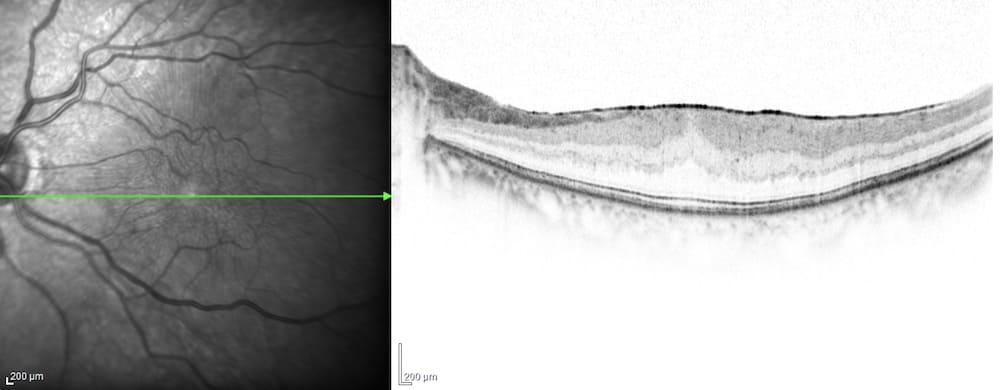

黄斑円孔は、網膜の中で視力に重要な黄斑部に小さな穴(円孔)が空く病気です。加齢などによって硝子体が縮むときに、網膜が一緒に牽引され(引っ張られ)、黄斑部に亀裂が生じ、穴が空きます。進行具合によって症状は様々ですが、急に視力が悪くなったり、視野の中心が黒く見えたり、物が歪んで見えたりします。硝子体手術で、原因となった硝子体を切除し、眼の中にガスを入れて円孔を塞ぎ、視力の改善を図ります。